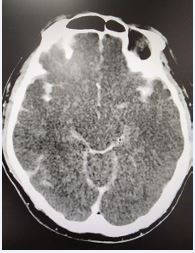

There was no evidence of external injuries. The blood tests showed Troponin T of 314 ng/dl and was significantly elevated. Creatinine, electrolyte, urea, hemoglobin, sugar and blood counts were normal. A toxicology screening was found to be positive for meth (cut-off level 500ng/ml) and benzodiazepine (cut-off level 200ng/ml) in the urine sample. The blood alcohol level was 2.2 mmol/L. The blood culture for bacteria, fugus and various virus panels was negative. The brain CT showed massive supra and infra tentorial subarachnoid hemorrhage (SAH) with extension into the ventricles without dilatation (Figure 2).

Figure 2: Computer Tomogram Head showing grade 4 sub arachnoid hemorrhage in the brain.

There was no evidence of head injury or cerebral ischemic stroke. Intensive care management was continued for his critical condition and despite efforts and supportive measures, he passed away on day 3.